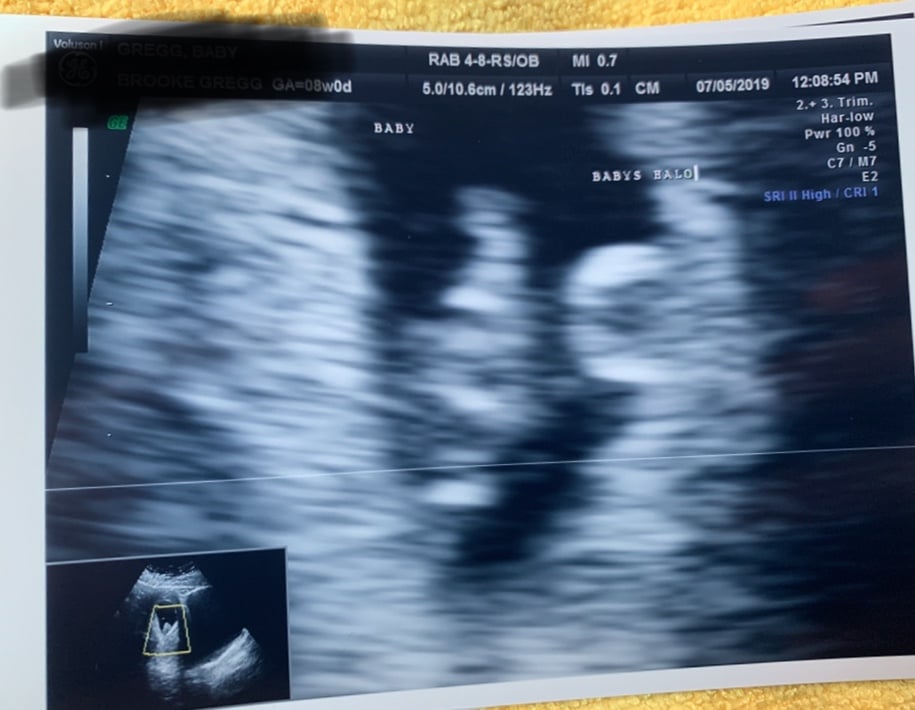

I had my first OB appointment today and got my first picture of my “bat” baby. I call him/her my bat baby because s/he is chillin’ upside down 🤪 HR was strong at 171. I just love this little bat baby already 🥰